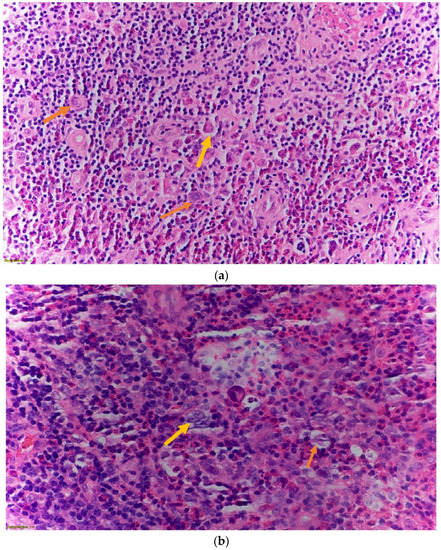

2. Case Presentation